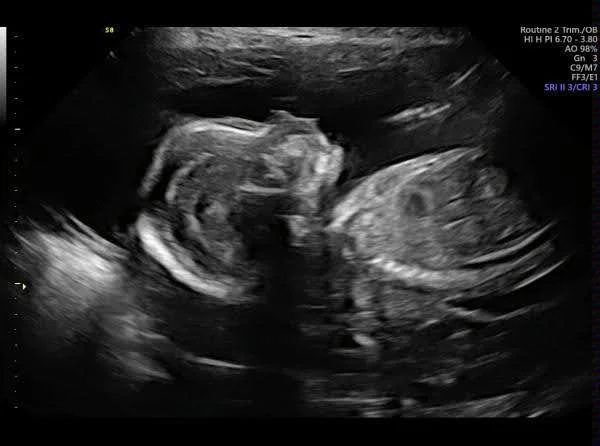

I am here to help you navigate the perinatal period (the time frame from conception through the first year after giving birth) and adjustment to motherhood. This period of time is a huge adjustment and almost everyone feels some level of anxiety and emotional instability during it. It is common to feel a range of emotions during this period: happy, love, excitement, anxiety, sadness, mourning the loss of your old life, guilt, etc… And it is common for these feelings to fluctuate minute-by-minute.